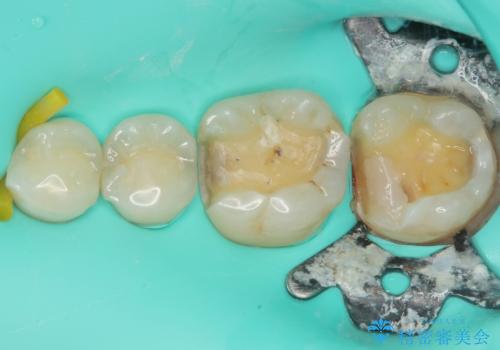

拡大鏡視野下で、金属の詰め物(メタルインレー)、保険のプラスチック、虫歯の除去を行い、セラミックインレーに適した形に整えました。

歯と歯茎の間に圧排糸と言われる糸を入れてシリコーン印象材にて精密な型どりをしました。

セラミックインレーの装着時には、唾液の侵入を防ぐために、ラバーダム防湿を行いました。